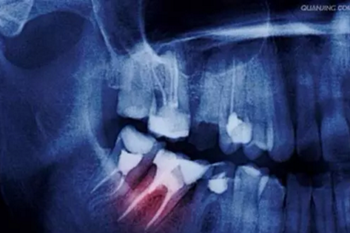

5、不愿意拍牙片

一些人不愿意照牙片,認(rèn)為醫(yī)生看看牙齒情況就可以了。

要知道醫(yī)生的眼睛不是透視鏡,牙齒好比大樹,樹根扎在土壤里,而我們的牙根也埋在牙槽骨里,牙根的狀態(tài)、里面的神經(jīng)肉眼都是看不到的。

只有通過牙片,牙醫(yī)才可以確切了解齲壞的范圍、牙痛是由牙髓炎還是根尖炎或是牙周炎引起、種植牙需要的骨量等等。

牙疼才去看牙?牙科最良心科普都在這里了!

圖:種植牙牙片

牙片為醫(yī)患溝通提供了準(zhǔn)確的依據(jù)。

有些家長(zhǎng)還認(rèn)為孩子拍牙片會(huì)受到輻射,對(duì)身體不好,其實(shí)大可不必?fù)?dān)心,牙科X光片對(duì)身體輻射量相當(dāng)?shù)停⑶艺?guī)牙科都會(huì)配備防輻射服,影響微不足道。

建議

相信醫(yī)生,拍牙片只能對(duì)你有好處,也可以為你保留最原始資料,更可以讓醫(yī)生準(zhǔn)確判斷你的病情,更好地為你治療。